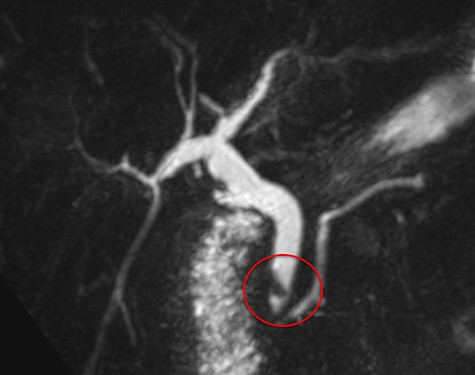

A 71-year-old woman with a history of LC for acute cholecystitis 6 years earlier was admitted with right upper quadrant abdominal pain, jaundice and fever. On admission, her vital signs were body temperature 38.2°C, pulse rate 96/min, respiration rate 21/min, blood pressure 100/60 mmHg and SpO2 98%. Her laboratory tests showed leukocytosis (19.200/ml), an erythrocyte sedimentation rate of 25 mm/h, C-reactive protein of 26 mg/l and altered liver function tests with cholestatic pattern: total bilirubin 4.95 mg/dl (normal up to 1.2), direct bilirubin 4.18 mg/dl, alkaline phosphatase 1083 IU/l (normal up to 150), gamma-glutamyl transferase 169 IU/l (normal up to 45), aspartate transaminase 281 IU/l (normal up to 40) and alanine transaminase 330 IU/l (normal up to 41). Serum amylase and lipase were normal. Abdominal ultrasound showed biliary tract dilatation but not obstructive cause, with a maximum diameter of the CBD of 17.6 mm. A subsequent magnetic resonance cholangiopancreatography (MRCP) found a filling defect in the distal CBD (Fig. 1). ERCP extraction was attempted, but it was impossible to progress the catheter due to an irregular distal bile duct stenosis. An abdominal computed tomography (CT) scan was therefore performed and showed a foreign body with radiopaque characteristics in the distal CBD consistent with a metallic clip (Fig. 2). Given that the object could not be removed by ERCP due to technical difficulties in biliary cannulation, laparoscopic bile duct exploration was decided.

Magnetic resonance cholangiopancreatography (MRCP) showing a filling defect in the distal bile duct (red circle).